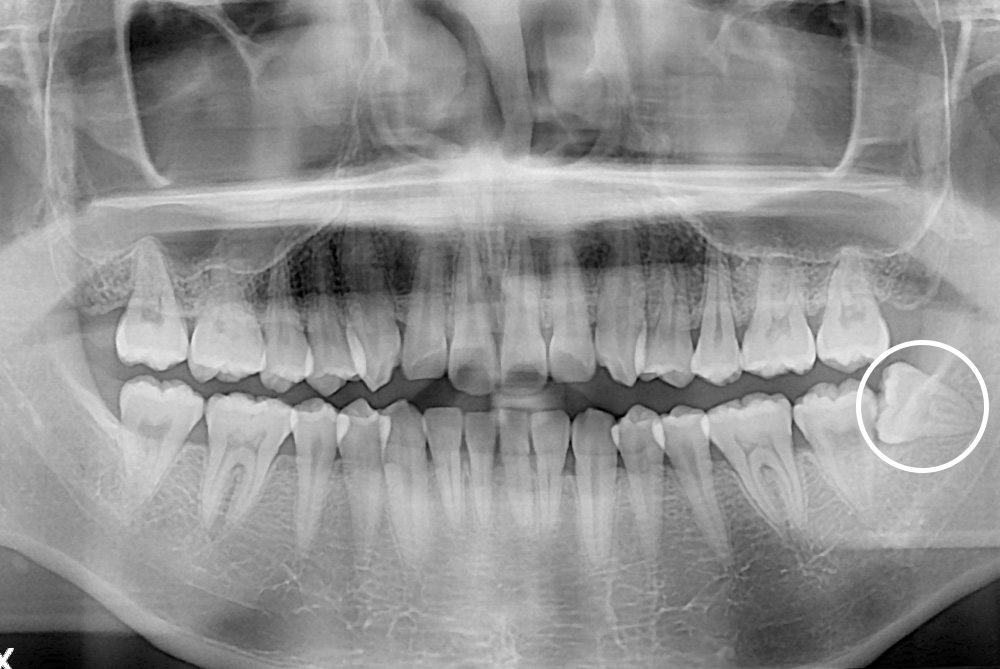

[사랑니] 매복 사랑니 발치

치료후 : 2019-02-20

세종치과는 구강악안면외과학 박사이신 원장님이 발치하는 치과입니다.